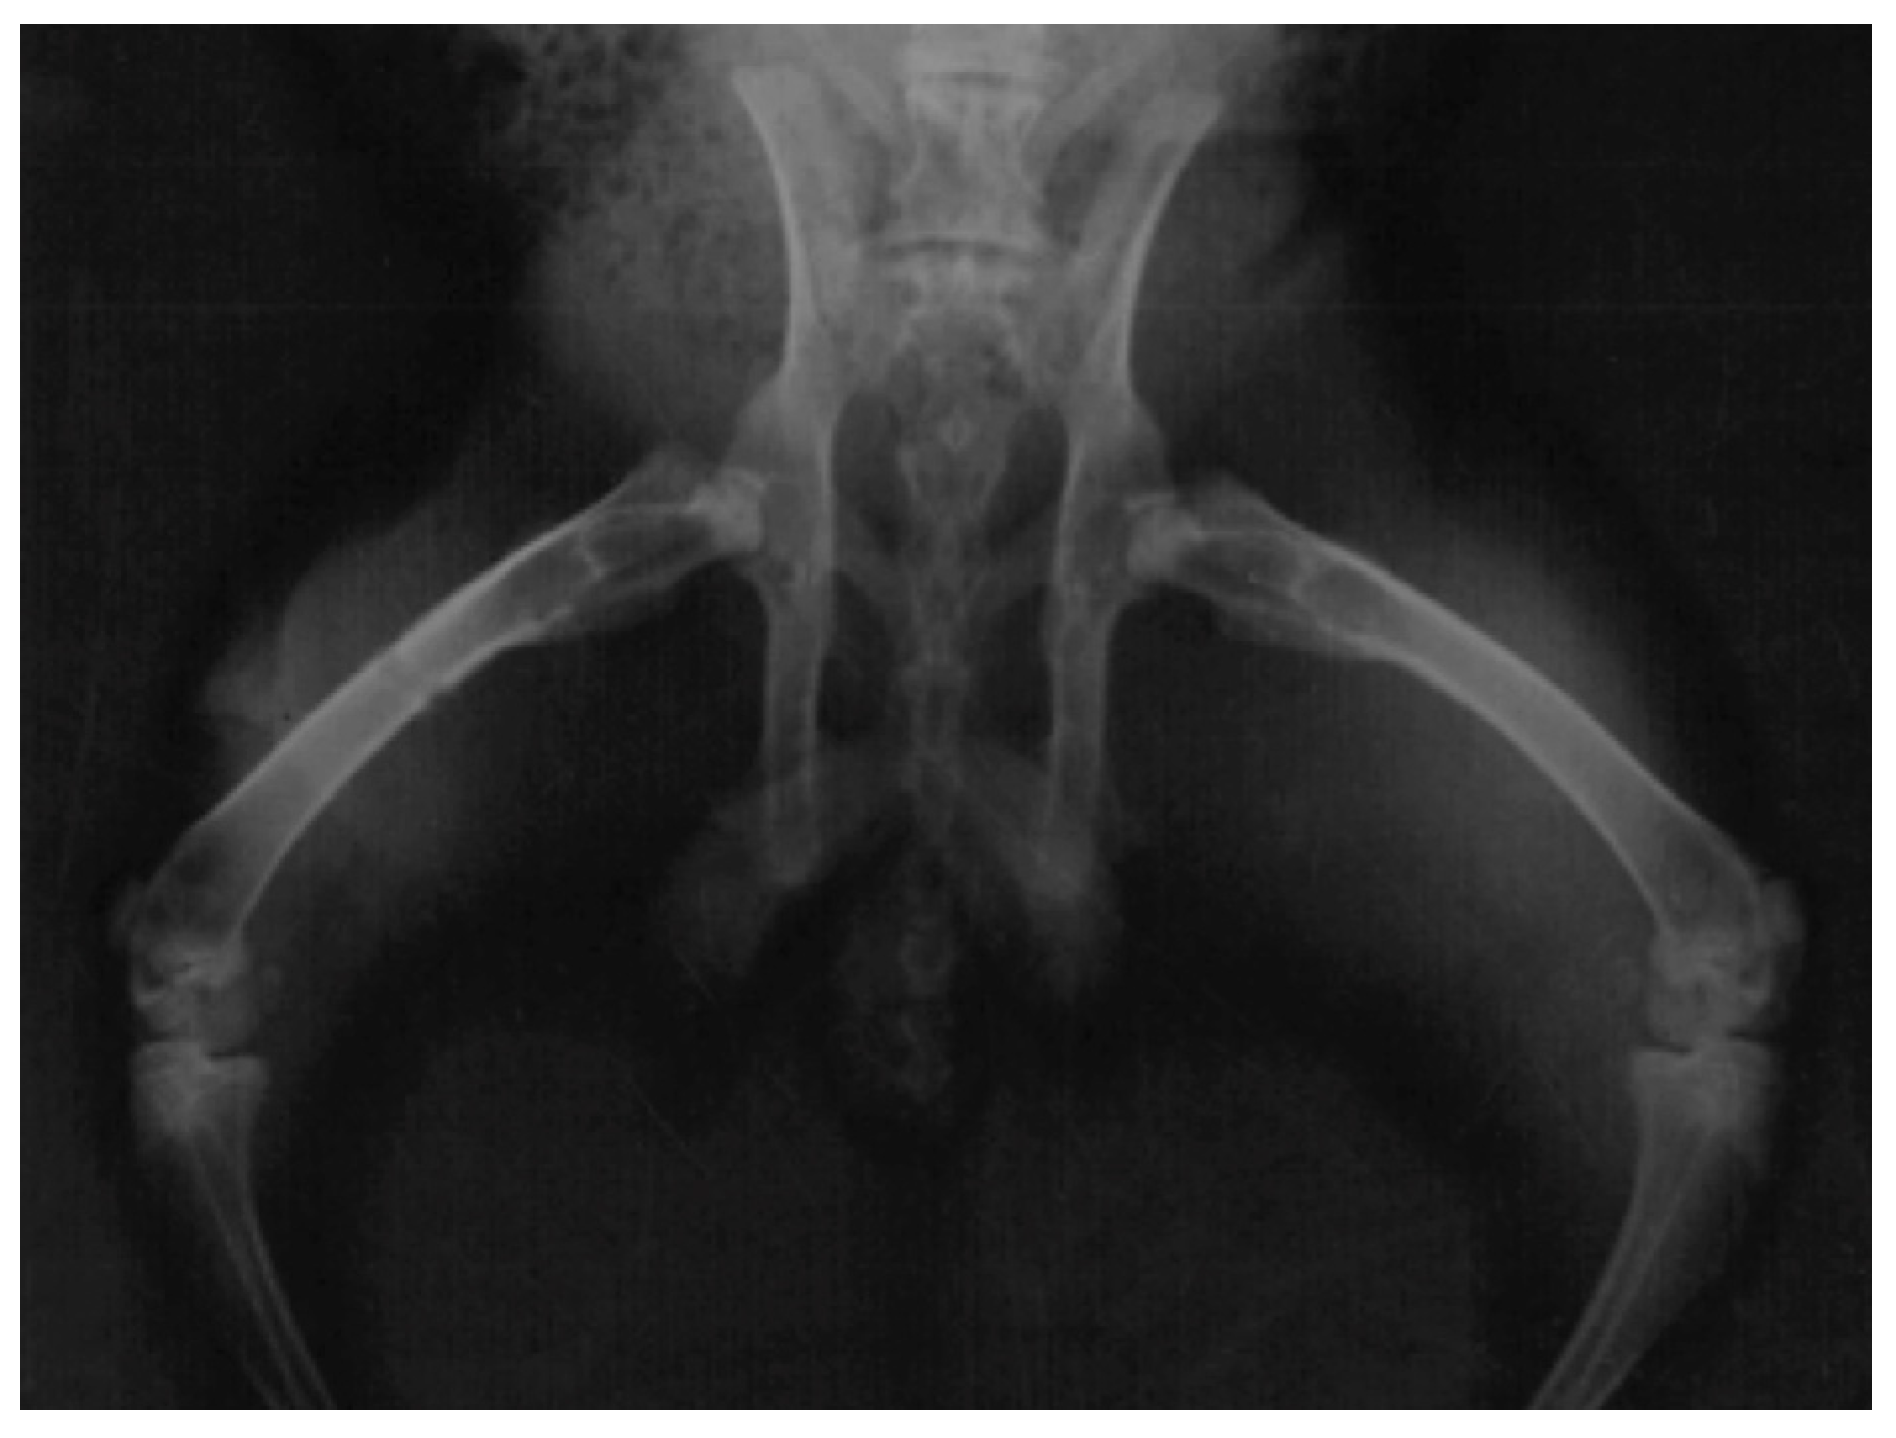

3.4. Radiographic Assessment

The main radiographic findings among the animals with infection were bone remodelling with thickening of the periosteum and surrounding sclerosis (Figure 3). No bone sequestra was noticed. Animals with clinical findings of foreign-body reaction had similar radiologic appearance. Ten healthy animals in Group B also had periosteal thickening, while the remaining healthy animals in both groups had normal radiographic appearance and no bone reaction (Figure 4).

Figure 3.

Radiograph of a rabbit with a titanium plate which developed an infection. A small periosteal reaction is apparent (red arrows).

Figure 4.

Radiograph of a healthy rabbit with an absorbable plate on the right femur and no bone reaction.